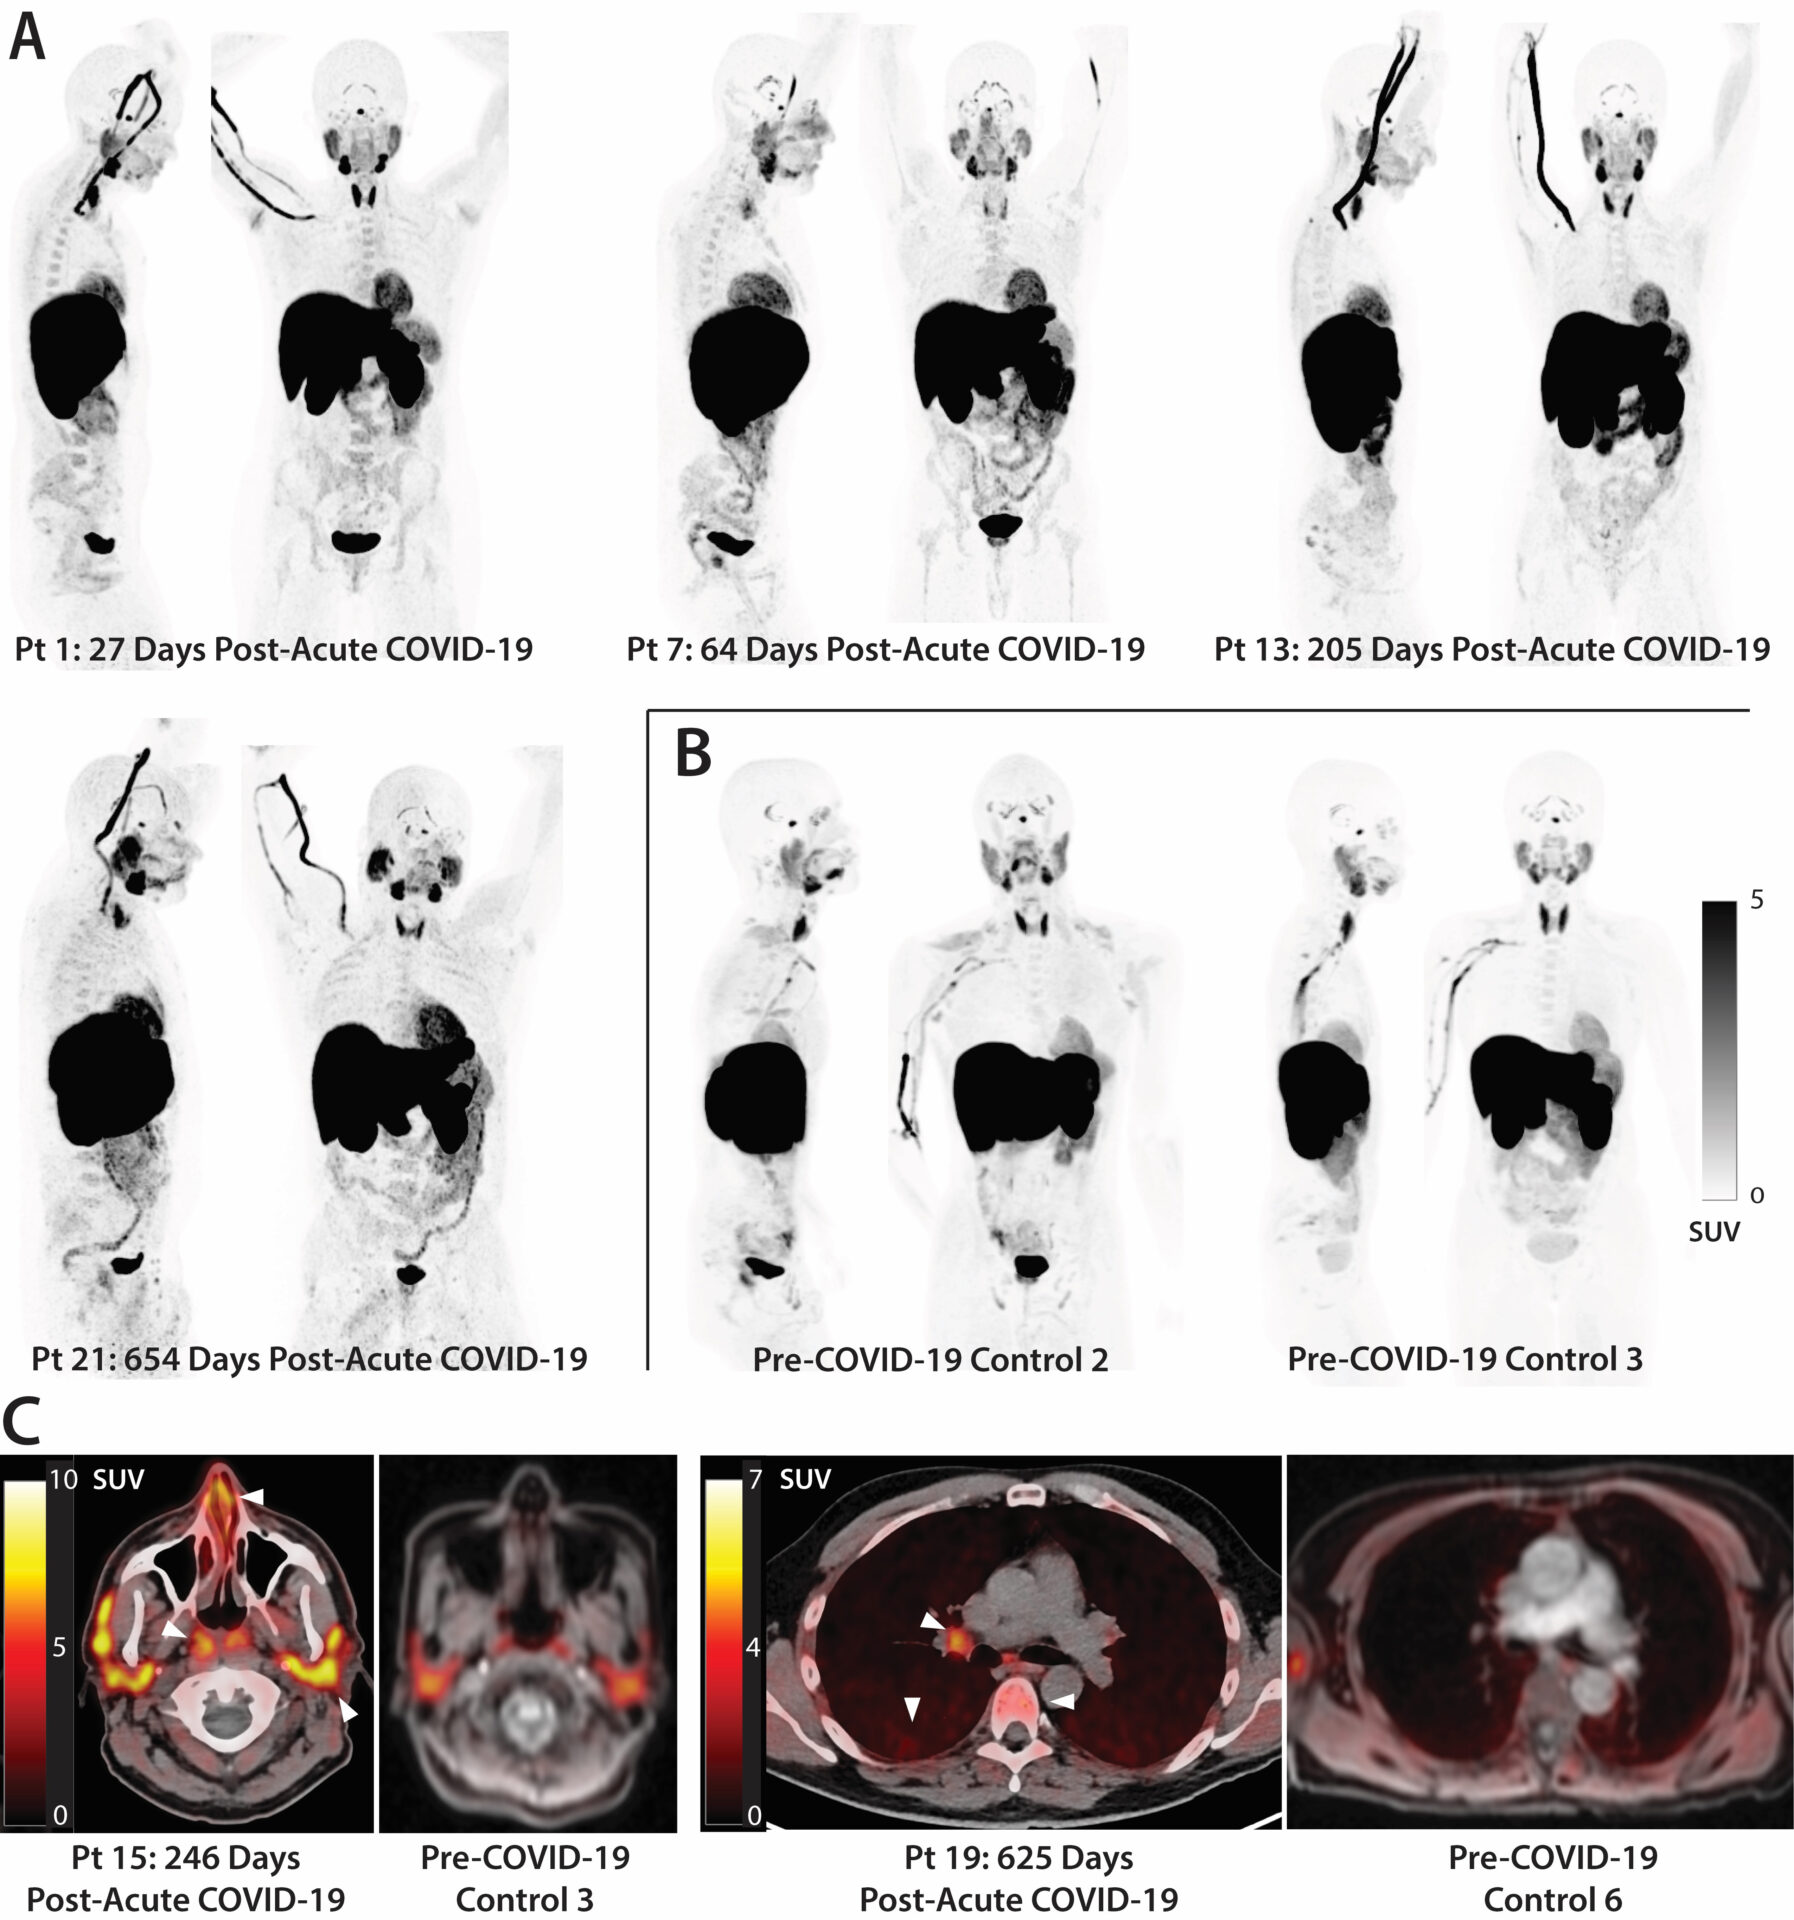

Στη συγκεκριμένη έρευνα συμμετείχαν 24 άτομα που υποβλήθηκαν σε τομογραφία PET σε όλο το σώμα τους. Οι συμμετέχοντες είχαν νοσήσει με Covid-19 από 27 έως 910 ημέρες πριν από την έρευνα. Όπως διαπιστώθηκε, οι ασθενείς που ανάρρωσαν παρουσίαζαν έντονα σημάδια ενεργοποιημένων Τ κυττάρων στο εγκεφαλικό στέλεχος, τον νωτιαίο μυελό, τους ιστούς της καρδιάς και των πνευμόνων και πολλά άλλα σημεία του σώματος. Επιπλέον, αυτή η ενεργοποίηση των κυττάρων συσχετίστηκε με τα μακροχρόνια συμπτώματα Covid. Για παράδειγμα, τα άτομα που ανέφεραν επίμονα προβλήματα στους πνεύμονες παρουσίαζαν ισχυρότερα σημάδια ανοσολογικής ενεργοποίησης στους πνεύμονες.